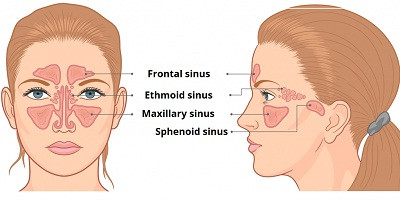

Бактеріофаги в лікуванні хронічних риносинуситів, резистентних до терапії

У журналі Antibiotics опубліковано огляд, присвячений перспективам та проблемним аспектам застосування бактеріофагів у пацієнтів з хронічним риносинуситом стійким до терапії. В огляді наведено результати доклінічних та клінічних досліджень у цій сфері